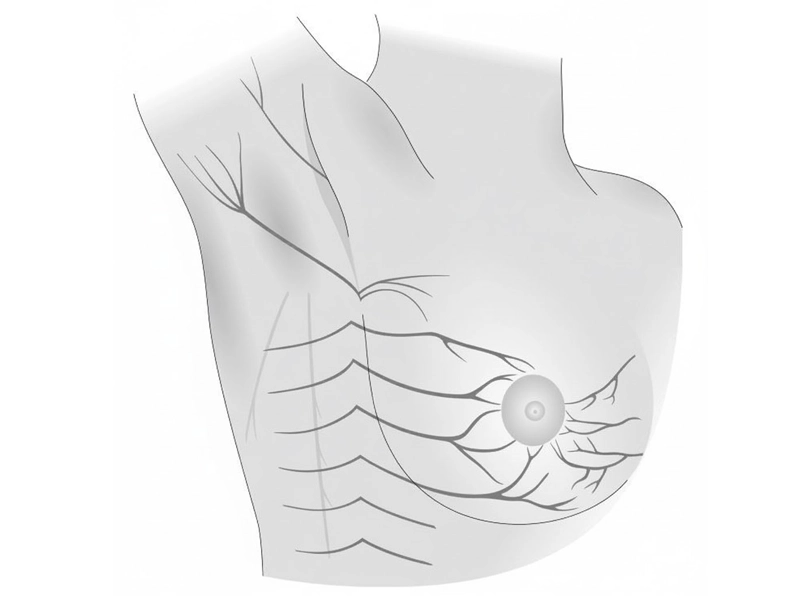

۲) تسلط کامل بر انکوپلاستی (Oncoplastic Breast Surgery)

این یکی از مهمترین مزایای نسل جدید جراحان پستان است:

• ترکیب جراحی سرطان با طراحی دقیق زیبایی

• مهارت در ماموپلاستی درمانی

• بازسازی فوری یا تأخیری بدون نیاز به ایمپلنت

• حداقلسازی اسکار

• راهکارهای حفظ NAC و حفظ فرم طبیعی پستان حتی در جراحیهای گسترده

این سطح از مهارت، جراحی سرطان پستان را از یک عمل صرفاً «حذف توده» به یک عمل بازسازانه، دقیق و هنرمندانه تبدیل کرده است.